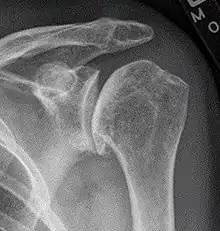

The shoulder joint is composed of three bones: the clavicle (collarbone), the scapula (shoulder blade), and the humerus (upper arm bone) (see diagram). Two joints facilitate shoulder movement. The acromioclavicular (AC) joint is located between the acromion (part of the scapula that forms the highest point of the shoulder) and the clavicle. The glenohumeral joint, to which the term "shoulder joint" commonly refers, is a ball-and-socket joint that allows the arm to rotate in a circular fashion or to hinge out and up away from the body. The "ball" is the top, rounded portion of the upper arm bone or humerus; the "socket," or glenoid, is a dish-shaped part of the outer edge of the scapula into which the ball fits. Arm movement is further facilitated by the ability of the scapula itself to slide along the rib cage. The capsule is a soft tissue envelope that encircles the glenohumeral joint. It is lined by a thin, smooth synovial membrane.